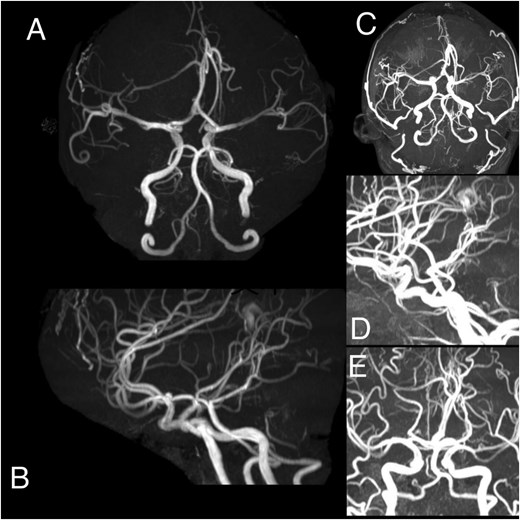

A 23-year-old male presented to our hospital with a 3-day history of episodic left upper limb paralysis. Upon admission, he reported progressive left lower limb motor incoordination, temporal visual field defects in the left eye, bilateral vision,deterioration, and bilateral olfactory hypesthesia over the preceding 3 months. Three days prior to admission, he experienced sudden-onset left upper limb paralysis lasting ~10 minutes before spontaneous resolution. Cranial magnetic resonance imaging (MRI) revealed a giant meningioma (>8 cm in diameter) causing extensive compression of adjacent structures, with marked heterogeneous enhancement on contrast imaging (Fig. 1). Preoperative intracranial vascular embolization was performed, followed by tumor resection via a bifrontal-parietal approach 1 day later (Fig. 2). Intraoperative findings confirmed a tumor >8 cm in diameter with cranial bone erosion (Fig. 3). Postoperatively, the patient developed transient bilateral lower limb paralysis (muscle strength grade 0) on Day 1, which resolved completely within one month. Histopathological analysis demonstrated features consistent with atypical meningioma: sheet-like growth pattern, increased nuclear-to-cytoplasmic ratio, prominent nucleoli, focal necrosis, and immunohistochemical staining showing Vimentin(+), SSTR2(+), PR(+), EMA(−), and a Ki-67 proliferation index of 5%–10%. The patient underwent gamma knife radiosurgery at 6 months and 1 year postoperatively. Three-year follow-up MRI showed no tumor recurrence or significant progression of residual lesions (Fig. 4), with significant improvement in visual acuity, hearing, and visual field deficits.

(A–E) Angiography demonstrates a hypervascular space-occupying lesion supplied by branches of the right anterior cerebral artery, right middle meningeal artery, right superficial temporal artery, left anterior cerebral artery, left middle meningeal artery, and left superficial temporal artery.

Due to the tumor's massive size and hypervascularity, preoperative arterial embolization was performed. While preoperative embolization has been shown to reduce surgical complications and long-term disability rates, conclusive evidence supporting its efficacy in minimizing intraoperative blood loss remains limited [9–11]. Atypical meningiomas exhibit high 5-year recurrence rates of 40%–60%. However, follow-up evaluations at 1 and 3 years in this case revealed no tumor recurrence or significant progression of residual lesions, suggesting personalized treatment strategies may transcend traditional prognostic frameworks. This outcome underscores the efficacy of multimodal therapy (embolization + surgery + radiotherapy) and aligns with the hypothesis that individualized approaches could improve outcomes beyond conventional expectations. Notably, the absence of recurrence at 3-year follow-up contrasts with the typical 40%–60% recurrence rates reported in literature, further supporting the potential of tailored therapeutic regimens.